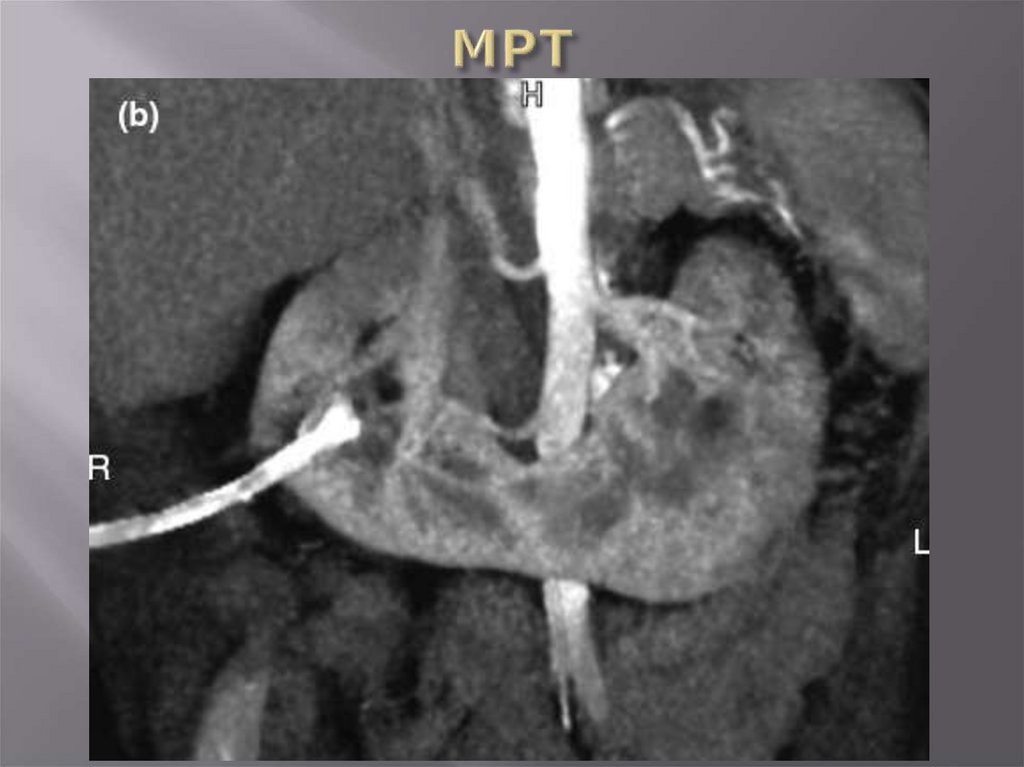

Лучевые методы (УЗИ, допплер,

рентгеноконтрастные методы,

радиоизотопные методы, КТ, МРТ)